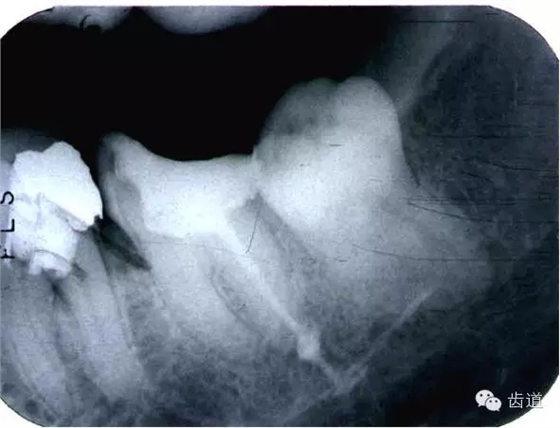

左上5牙頸部側(cè)穿

左下6底穿

左上6底穿

左上4鑄造樁側(cè)穿